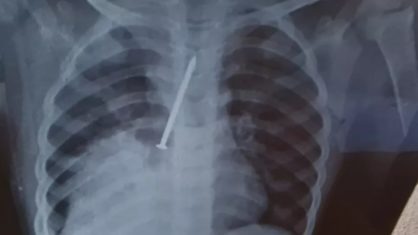

A mãe de Cauan, então, realizou o raio-x solicitado pela médica durante a primeira consulta. O exame comprovou que a criança engoliu um prego de 10 centímetros.

Os médicos identificaram que o material havia perfurado os dois pulmões de Cauan. Ele chegou a ficar internado dois dias na UTI, mas não resistiu.